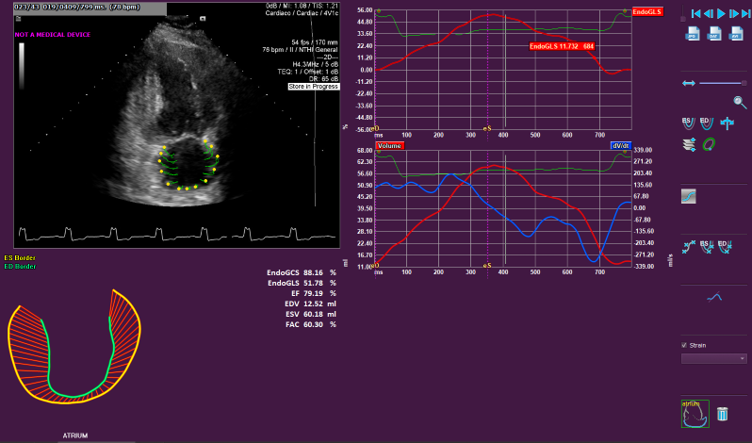

- Allows the quantitative evaluation of the Left Ventricle, Right Ventricle and the Left Atrium OEM solution. See the applications below for further details